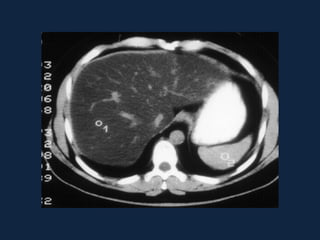

ESTEATOSE HEPÁTICA

MULTINODULAR

• Forma mais rara de esteatose hepática.

• É fundamental a correlação com dados

clínicos e com estudos de RM para excluir

doença metastática.